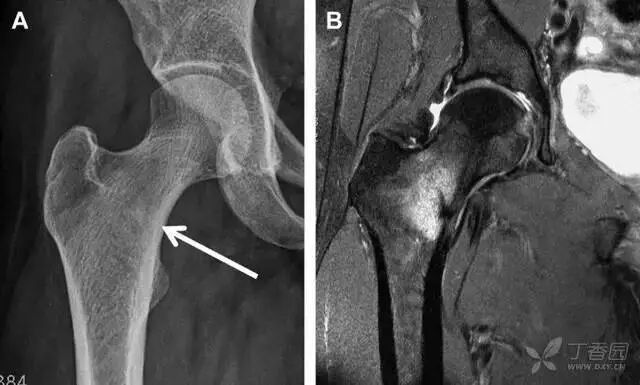

尽管仔细检查和评估,仍有一些外伤后髋部疼痛的患者,存在 X 片上难以发现的隐匿性髋部骨折。这种情况下,可以选择对骨髓水肿高度敏感的 MRI 进行随访(图 1)。

图 1 长跑运动员股骨隐匿性、应力性骨折。A 为髋部正位 片,虽未见明显骨折,但股骨颈基底部可见一模糊的线性硬化带(箭头)B 为 MRI 冠状位 STIR 序列扫描,示股骨颈应力侧可见一线性低密度信号影,周围包绕骨髓水肿的高密度影

从这个案例来看,长期运动的患者,如果出现髋部疼痛,X 线即使无特殊表现,也应考虑应力性骨折的可能性。

股骨颈应力性骨折

股骨颈应力性骨折在参加耐力运动的运动员中常见,且常发生在股骨颈压力侧。股骨颈基底部发现一垂直于骨皮质的线性硬化带可诊断这种类型的疲劳性骨折(图 8)。

图 8 长跑运动员股骨颈应力性骨折。X 片(A)和冠状位 CT 多维重建(B)图像示穿过股骨颈内侧皮质中的透亮区(箭头),周围硬化。骨折垂直于皮质